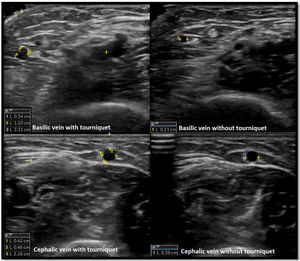

Venous evaluation includes demonstration of patency. This is achieved by applying pressure to the transducer and totally compressing the vein. Besides patency, vein diameter is also measured (Fig. 2) as many studies demonstrated that this parameter has implications for prognosis of the access. The existing guidelines do not define a minimum acceptable vein diameter for AVF/AVG creation but it is generally accepted that diameter superior to 2mm is associated with better outcomes. Vein diameter changes with the use of a tourniquet can be measured, as this will provide information about venous distension capacity (distention capacity superior to 40% is a good prognostic factor).26–28 Also, any anatomical variation must be characterized as this may have implication when planning access construction (different drainage site, presence of accessory veins, different basilic vein course).21